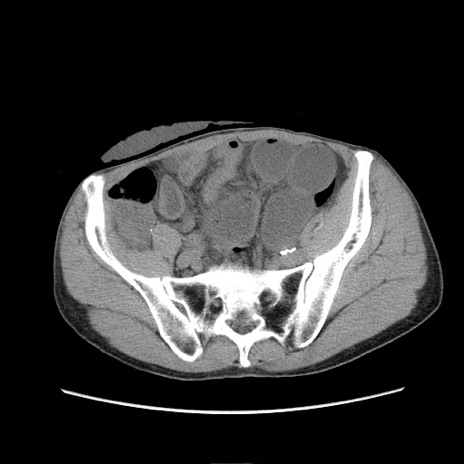

症例11(横断像)

【症例】 60歳代男性

【主訴】 下腹部痛

【現病歴】 本日夜中より下腹部痛の症状認め、受診。

【既往歴】 膀胱癌(膀胱全摘+尿管皮膚瘻術) 、胃癌術後

【身体所見】 BT 35.3℃、PR 58/min、BP 136/98mHg、腹部平坦、軟、腸蠕動音±、ストマ留置あり、左上腹部~正中部に圧痛あり、反跳痛なし。

【データ】WBC 5100、CRP0.01